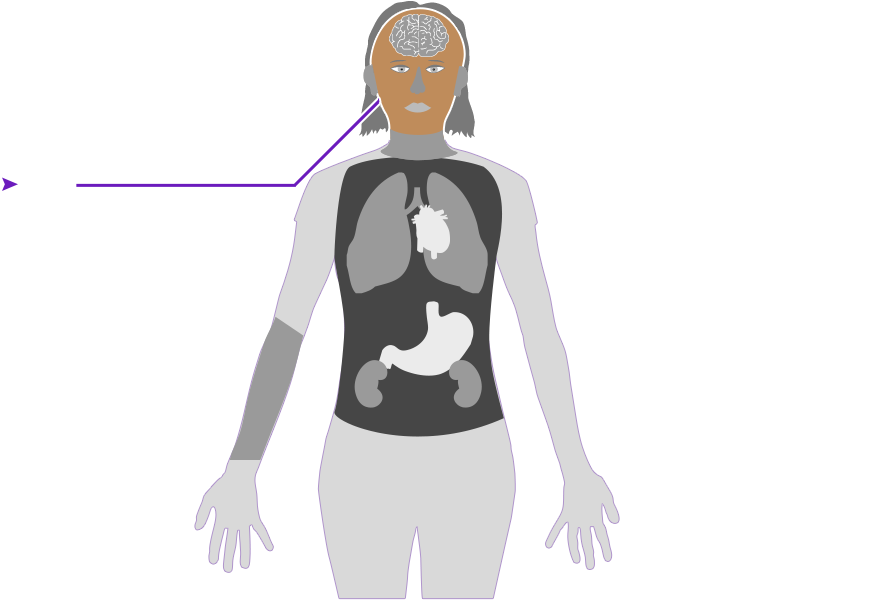

Check out how mercury can affect the human body. Click on the different parts of the body to see what can happen when people are poisoned by mercury. How serious these health effects are may vary depending on how much mercury gets into your body — and how long you breathe it in.

Health effect caused by breathing in high levels of mercury vapors (fumes) over a short period of time

Health effect caused by breathing in high levels of mercury vapors (fumes) over a short period of time  Health effect caused by breathing in lower levels of mercury vapors over a long period of time

Health effect caused by breathing in lower levels of mercury vapors over a long period of time